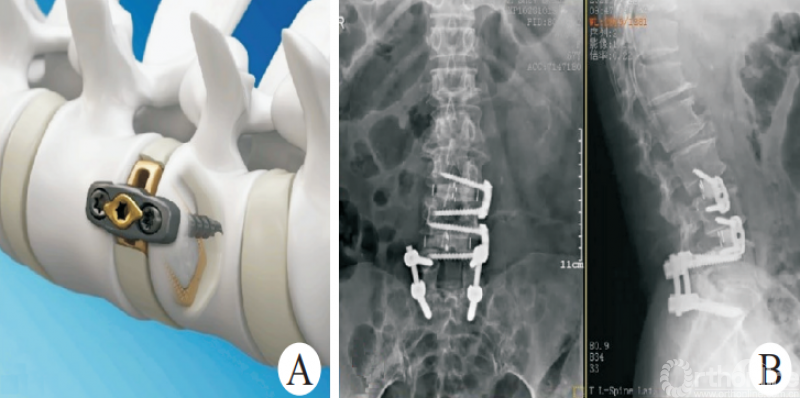

OLIF联合后路固定(1)是治疗脊柱滑脱等失稳性疾病的经典方式[5-9],在有效减压、恢复脊柱稳定性的同时,可以避免后方肌肉、韧带等结构的损伤。相关的研究对比OLIF以及经椎间孔入路腰椎椎间融合术(transforaminal lumbar interbody fusion,TLIF)手术治疗退行性腰椎滑脱,结果表明,两者在改善术后疼痛等方面没有明显差异,且具有住院时间短、出血量少、术后腰痛较轻等特点[10-12]

图1 经典的OLIF

CHUNG等[13]的研究表明,相较于前入路腰椎椎间融合术(anterior lumbar interbody fusion,ALIF)手术,OLIF在恢复椎间隙高度及节段前凸方面更加具有优势;葛腾辉等[14]研究证实,OLIF联合后路固定治疗退行性腰椎滑脱能进一步减少腰椎退行性滑脱患者的滑移率,并增加手术节段前凸角度。

俞仲翔等[6]研究证实,对于邻椎病的治疗,OLIF可以取得与后路腰椎椎间融合术(posterior lumbar interbody fusion,PLIF)等经典手术方式同样的效果,且能够缩短手术时间,减少并发症的发生。王志强等[15]研究证实,OLIF联合单侧或双侧的椎弓根螺钉固定均可有效治疗腰椎退行性疾病。CHO等[16]研究表明,对于存在矢状位失衡的退行性脊柱侧弯患者,OLIF联合后路螺钉治疗比传统的PLIF更加有效。因此,经典的OLIF技术可以应用于脊柱侧弯、脊柱滑脱、腰椎椎管狭窄等众多腰椎退行性疾病的诊疗。